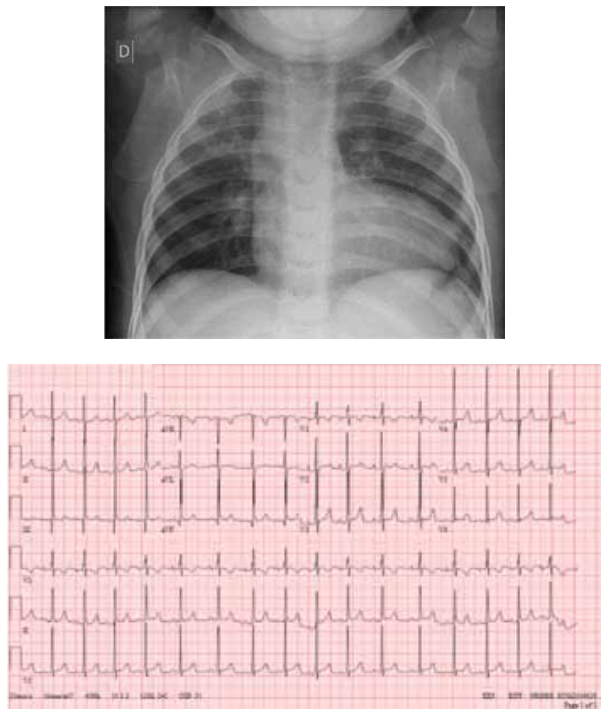

pulmões livres; abdome sem visceromegalias. Atualmente, encontra-se com 4 anos de idade, com estabilidade

hemodinâmica. Apresenta, a seguir, radiografia de tórax

e eletrocardiograma.

(Arquivo pessoal; imagens usadas com autorização)